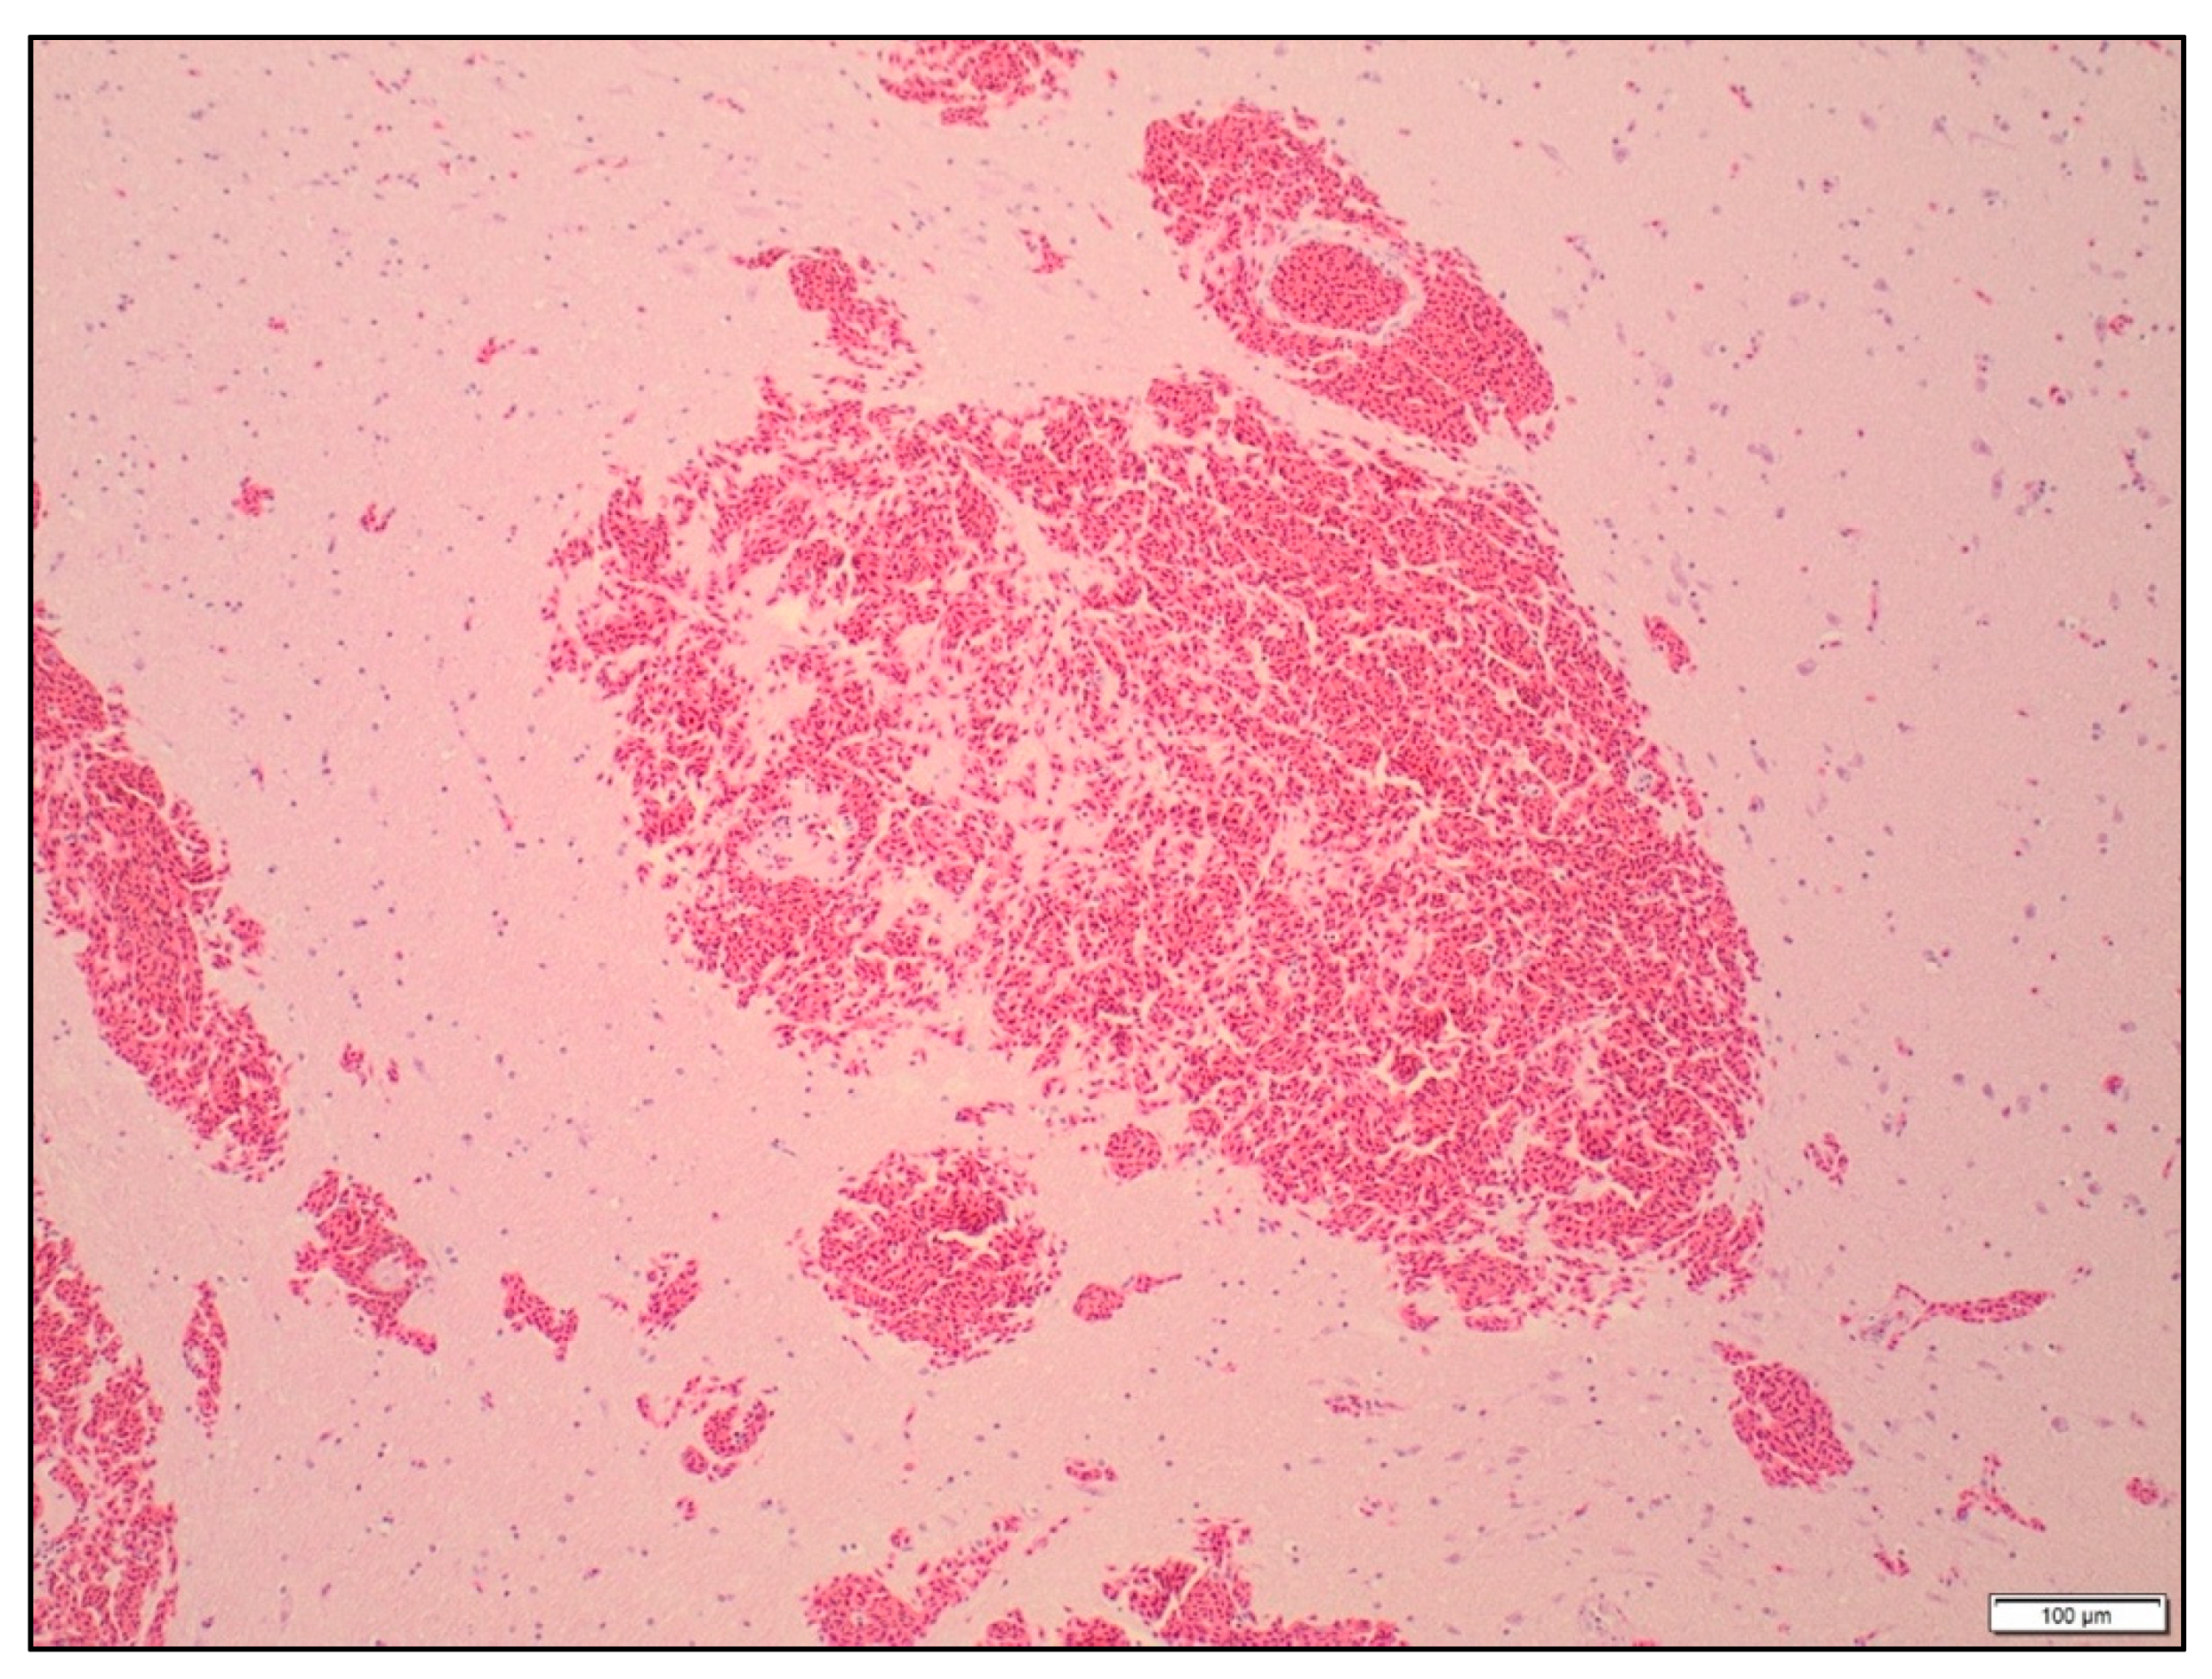

3.2.2. Microscopic Damage

All brain slices had some degree of subarachnoid haemorrhage over the surface of the brain (Figure 4). There was no significant difference in the severity of the haemorrhage between the treatments (p = 0.43). Petechial haemorrhage was evident in the cerebrums, thalamus and midbrain of all the birds, regardless of treatment (Table 4 and Figure 5). The frequency of petechial haemorrhage in the pons and medulla was slightly less in SAT shot birds (76% and 71% respectively) compared to those shot with the different configurations of the TED (ranging from 81 to 100%), however this difference was not significant. In addition to the petechiae, 100% of the brain slices in all groups showed congested blood vessels in all examined regions of the brain.

Figure 4. Focal subarachnoid haemorrhage over the cerebellum in a turkey shot with the SAT, ×240 magnification. Haematoxylin and eosin.